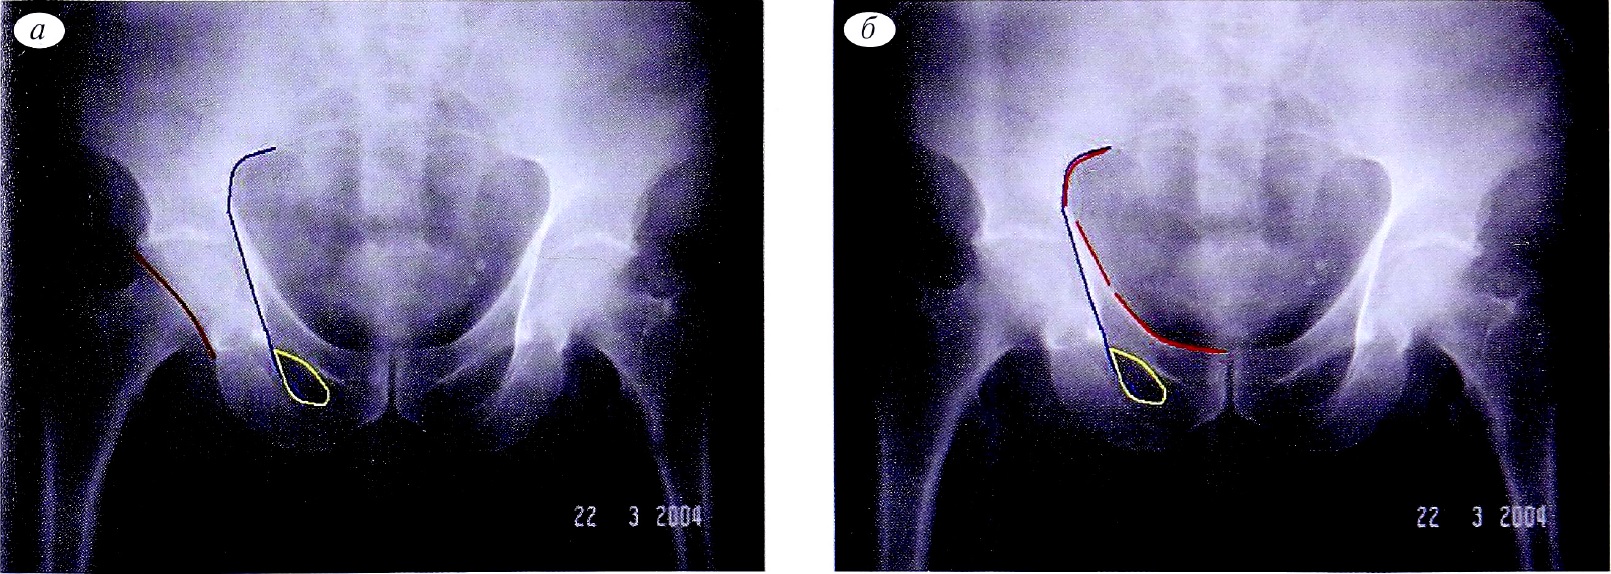

Определение типа перелома выполняют последовательным ответом на вопрос: имеется повреждение определенной линии или нет. Анализ контуров каждой референтной линии позволяет исключить определенные типы переломов. Основными линиями, позволяющими последовательно определить тип перелома, являются: подвздошно-гребешковая линия, подвздошно-седалищная линия, контуры запирательного отверстия, линия задней стенки, крыло подвздошной кости. Каждая из референтных линий на рентгенограммах отмечена определенным цветом (рис. 18).

Рис. 18. Цвета референтных линий на рентгенограммах.

Fig. 18. Reference lines colours on X-rays.